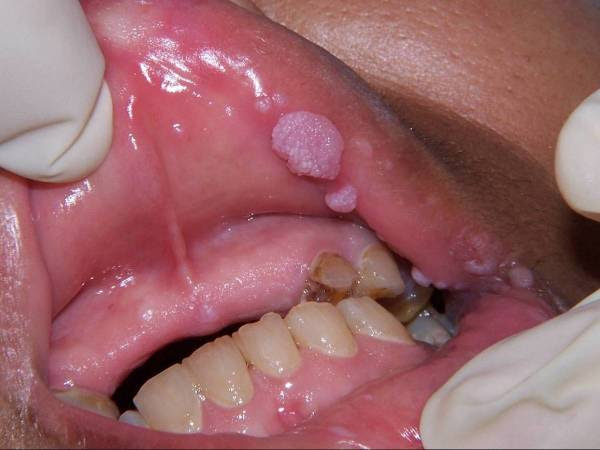

However, there is a disease that could possibly spread out even if they are using a condom. This is the disease called Human Papilloma Virus or the HPV. Dr. Nelly Mugo who is an expert when it comes to diseases such as STI said, “Condoms offer 60 per cent of HPV, thus the virus can spread through skin-to-skin contact with infected areas of the skin not covered by the condom such as the scrotum, anus, or vulva.”

There are a lot of types of HPV more than 100 exists, about 13 of them could possibly cause cancer. The only way to be safe from this is to remain abstinent and monogamous with their partners.